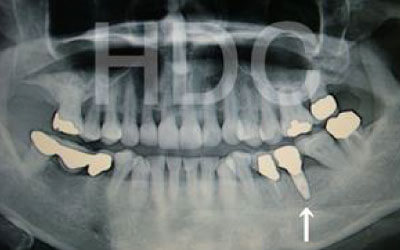

2 歯が傾いてくる、落ちてくる

歯はお互いに支え合ってバランスを取っています。ですので、歯が抜けるとその支えがなくなり、抜けた部分の隣の歯が倒れたり、上の歯が下に下がってくることがあります。

「少しずれた程度なら、噛み合わせを調整したり、小さな詰め物で修正することができます。

しかし、抜けてから数年経過して大きく歯が傾いている場合は、歯並びの矯正を行うか、歯を大きく削ってかぶせ物をする必要があります。